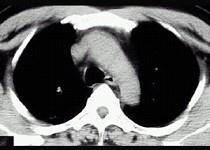

问题 21岁,近2个月来咳嗽,痰中带血丝,午后手心足底发热,盗汗、心悸,胸部CT见图,最可能的诊断是 ( )

选项 A.右上肺癌性空洞形成 B.继发性肺结核空洞形成 C.右肺脓肿 D.右上肺炎 E.肺囊肿

答案 B